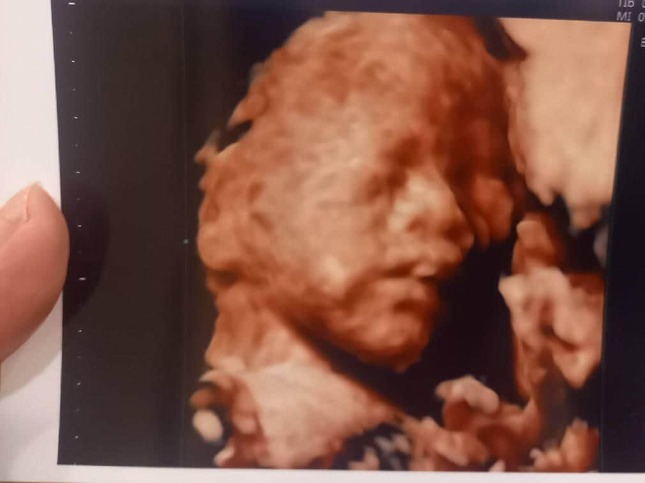

• 4Dエコー。赤ちゃんの顔がハッキリしてきた!

4Dエコー。赤ちゃんの顔がハッキリしてきた!